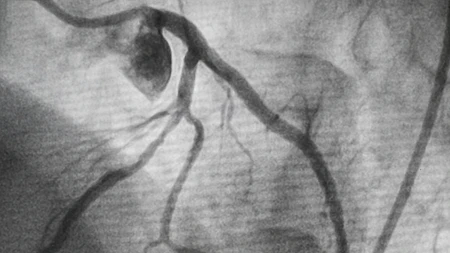

Einspruch zum Zweitmeinungsverfahren bei Aortenaneurysmen-Eingriffen